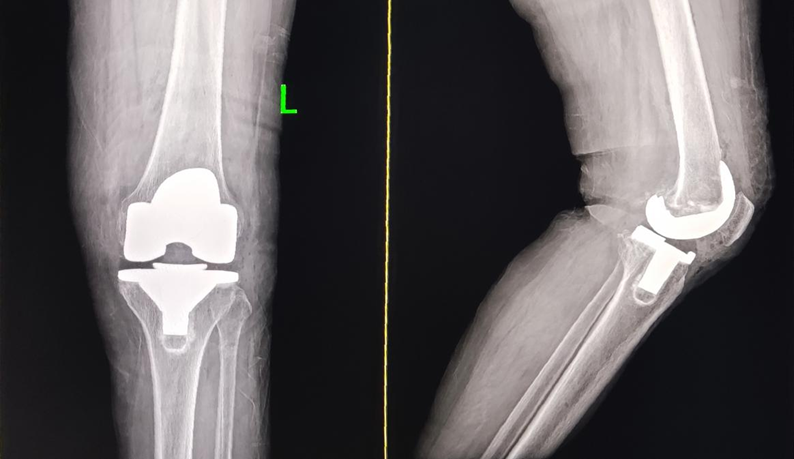

左膝术后

2025年12月、2026年4月,在医院手术团队的精心操作下,张阿姨先后成功接受了右膝、左膝关节置换手术。术后,医院依托先进的快速康复理念和责任制整体护理模式,为张阿姨制定了专属康复计划,医护人员每天定时查房、指导康复训练、关注身体恢复情况。

得益于科学的治疗康复方案和贴心的护理服务,张阿姨的康复效果十分显著,关节屈伸功能得到明显改善,多年的关节疼痛、肢体变形等症状消失,如今已能自主平稳行走。“做完手术变化太明显了,腿变直了,能自由屈伸,走路不疼也不晃了,终于能像正常人一样走路了,效果真的太好了!”张阿姨握着医护人员的手,由衷地赞叹道,言语间满是感激。